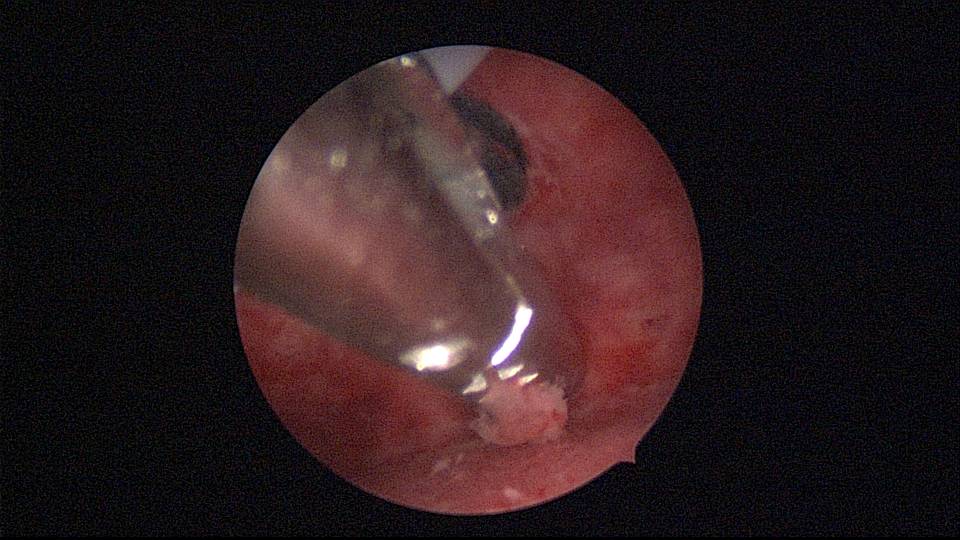

患者40岁,G0P0,原发不孕10+年,20+岁严重痛经,多家医院行腹腔镜手术治疗腺肌症合并多发性肌瘤,宫腔镜切除内膜息肉,前后肌注GnRH-a6针,痛经明显缓解。2017年试管助孕一次,失败,放弃生育需求,现要求放置曼月乐环并固定。2024年5月行宫腔镜下曼月乐不锈钢挂钩固定,子宫前位,宫深7cm,宫腔形态正常,宫内膜正常,双侧输卵管开口可见,将曼月乐环用4号丝线与挂钩连接并固定于宫底(第一次做宫腔镜下节育环固定,没有想到利用曼月乐尾丝连接环)。2024年6月复查B超,曼月乐固定装置扎入宫底肌层0.46cm,环位置正常,2025年5月复查B超,曼月乐顶端距宫底1.5cm。